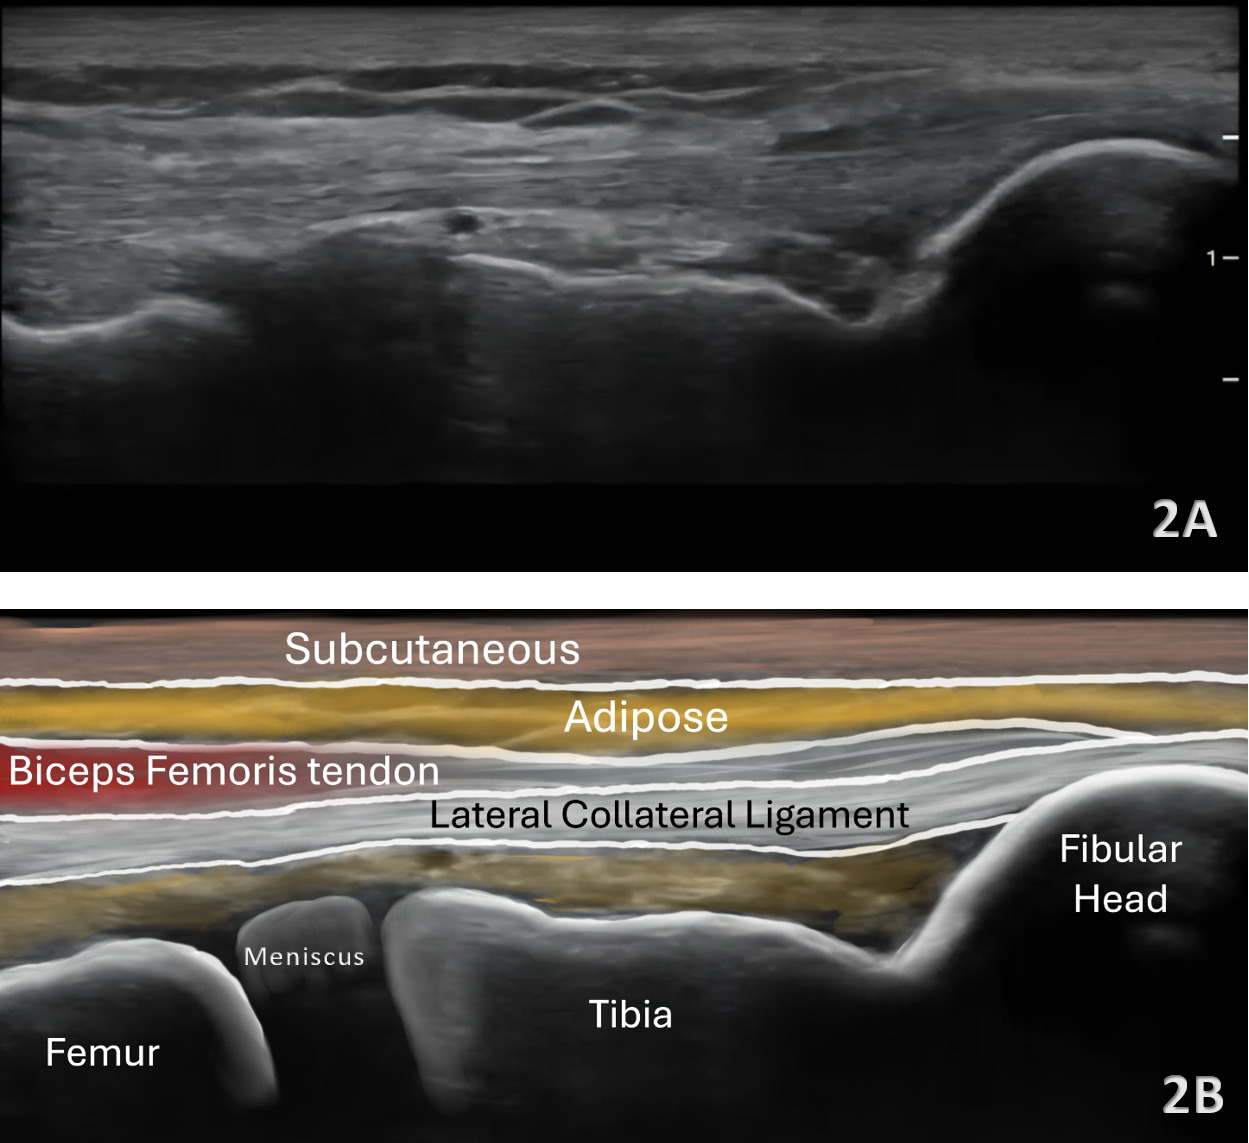

Lateral Meniscus

Figures 2A and 2B LAX View of Lateral Meniscus: The lateral meniscus demonstrates a triangular configuration but often appears slightly deeper and more curved than the medial meniscus. It lies beneath both the LCL and popliteus tendon, requiring careful angulation to eliminate anisotropy. Its increased mobility relative to the medial meniscus can be appreciated during subtle varus stress.